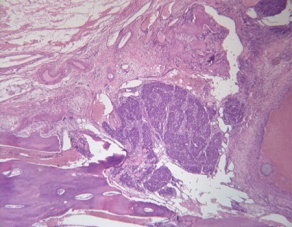

Renal Cell Carcinoma Metastasis